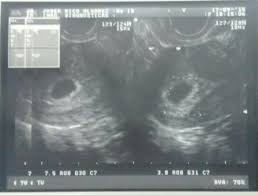

Embarazo Gemelar